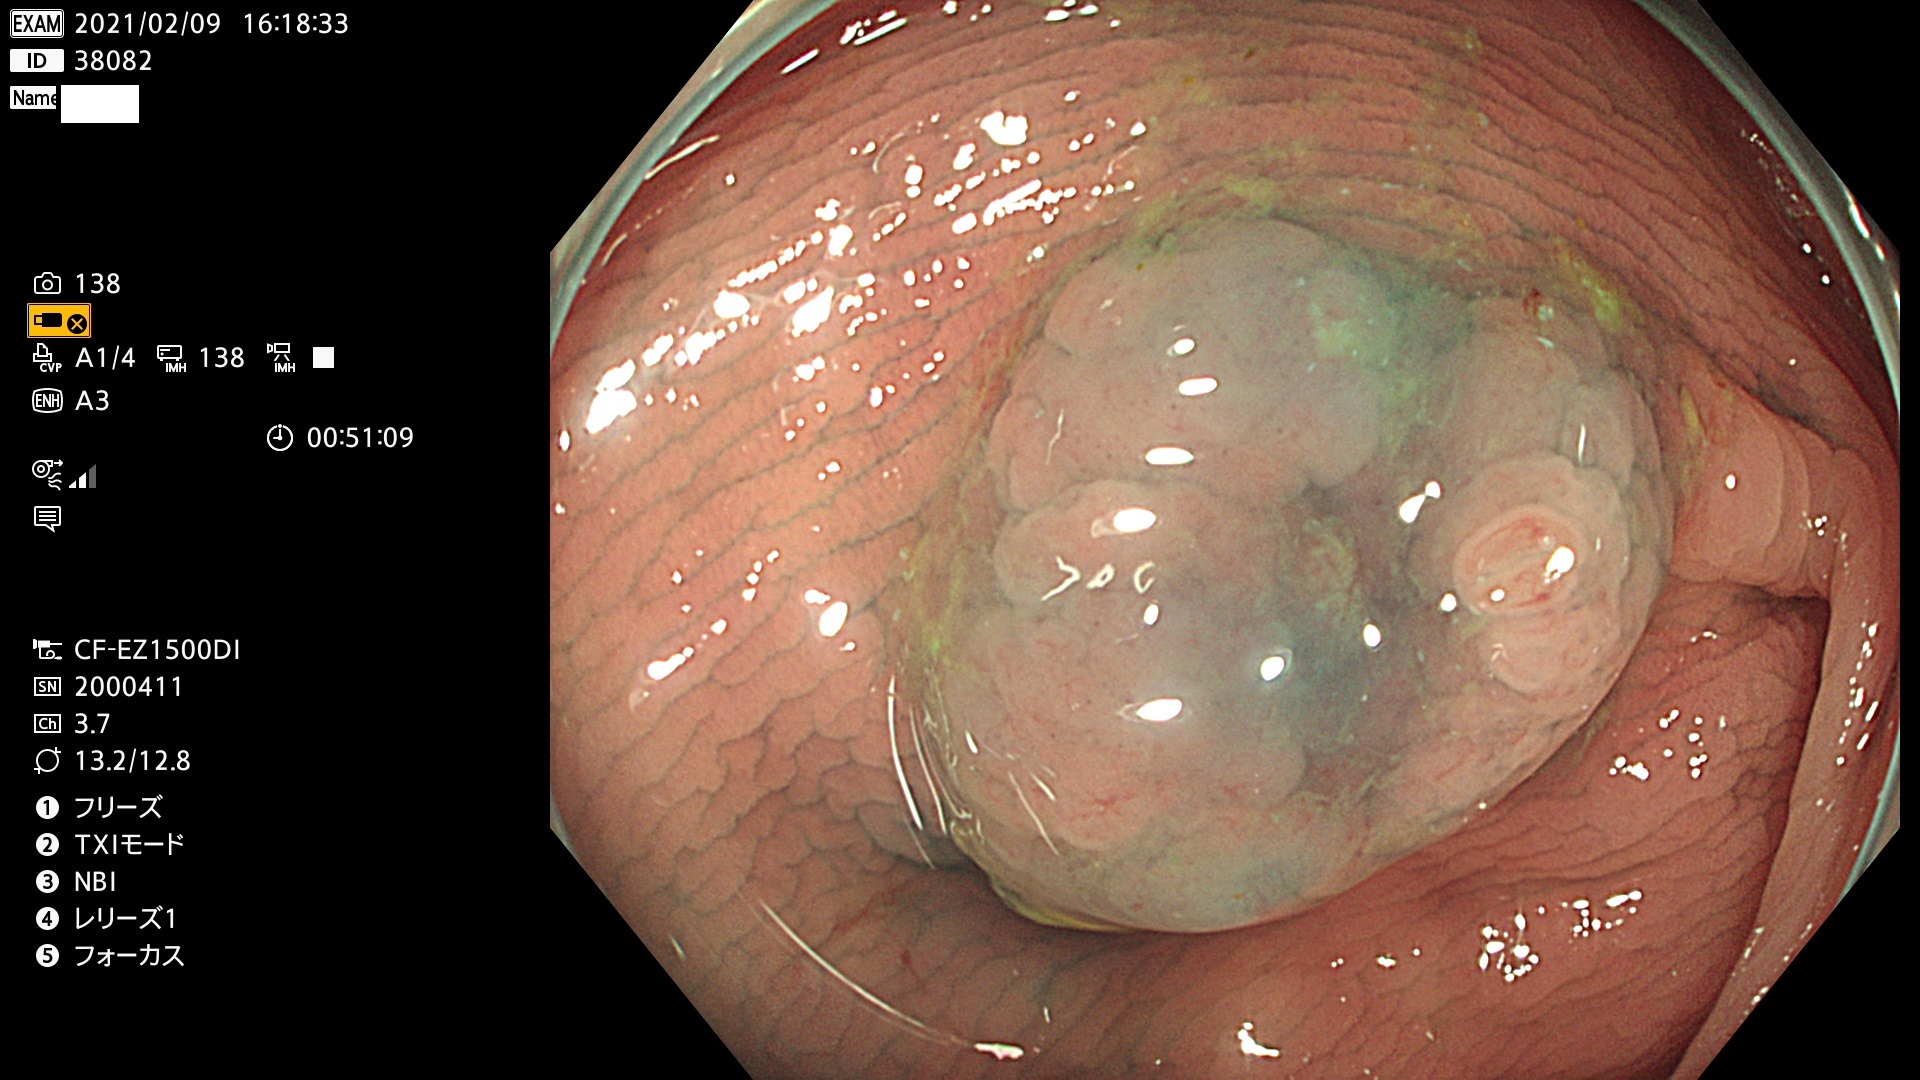

38001 38002 38003 38004 38006(SSAPのみ) 38007 38008 38009 38010 38012 38013 38014 38016 38018 38020 38021 38025 38026 38029 38032 38033 38034 38035 38036 38037(SSAPのみ) 38039 38043 38044 38048 38049 38050 38052 38055 38056 38057 38058 38059 38064(SSAPのみ) 38065 38068 38069 38070 38071 38072 38074 38075 38076 38078 38079 38080 38082 38083 38084 38085(SSAPのみ) 38086 38087 38088 38089 38090 38091 38092 38093 38094 38097 38098 38099

発見困難で危険性の高い平坦型病変(上記100名より抽出)